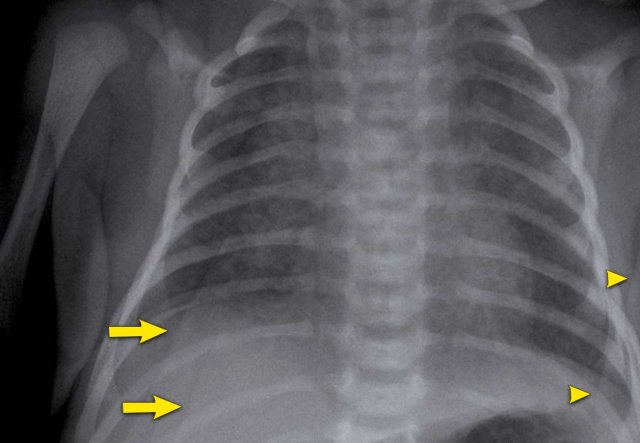

Image

A term newborn with an abdominal sepsis.

There are signs of fluid overload with accentuated blurry vessels. Skinfolds project over the right lower lung (arrows).

The lines cross anatomical borders, e.g. diaphragm and do not follow pleura or lungs.

Left arm projecting over hemi-thorax, resulting in sharp radiopaque line (arrowhead).